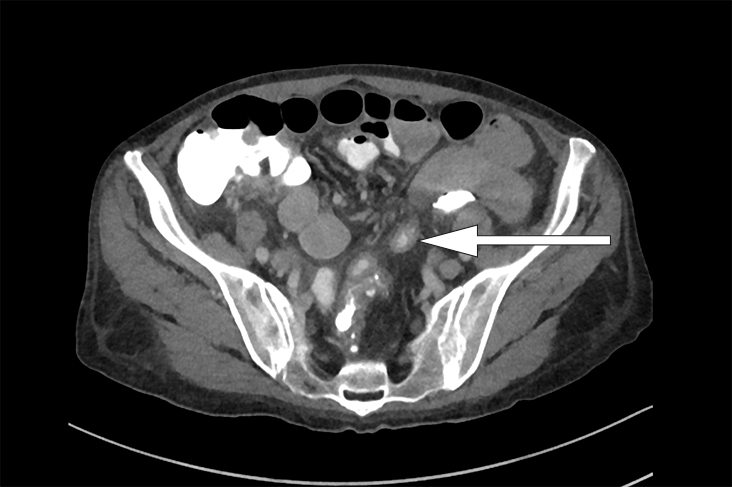

Én uke senere, i påvente av PET-undersøkelsen, ble pasienten reinnlagt grunnet diaré. Hun beskrev 6–8 vanntynne tømminger daglig uten synlig slim eller blod. Diareen var ledsaget av kvalme, men ikke oppkast eller magesmerter. Det var ingen relevant reise- eller medikamentanamnese, og ingen i omgivelsene hadde tilsvarende symptomer. Regranskning av CT-undersøkelsen fra forrige innleggelse viste, foruten mesenterial lymfadenopati, veggfortykkede tynntarmssegmenter (fig 1). Ved nærmere anamnese beskrev pasienten periodevis vanntynn/grøtaktig diaré de siste tre månedene samt 8 kg vekttap. Blodprøver viste INR 6,6 og reduksjon i serumalbumin fra 21,0 g/dl til 14,0 g/dl.

Konstellasjonen av migrerende leddsmerter og synovitter over flere år uten utvikling av radiologiske artrittforandringer, kombinert med intermitterende diaré og proteintapende enteropati gjorde at vi mistenkte Whipples sykdom, en sjelden infeksjonssykdom forårsaket av den grampositive bakterien Tropheryma whipplei. Pasienten ble henvist til gastroskopi og kapselendoskopi av tynntarm som viste betydelig inflammasjon med erosjoner, hemoragiske slimhinner og diffus lymfangiektasi (fig 2) (fig 3). Duodenalbiopsier viste breddeøkte totter og akkumulering av skummakrofager med periodisk syre-Schiff (PAS) diastasepositive granulære inklusjoner i cytoplasma (fig 4) (fig 5). Både de makroskopiske og histopatologiske funnene var godt forenlig med Whipples sykdom. PCR utført etter DNA-ekstraksjon fra parafininnstøpt tarmbiopsi var positiv for T. whipplei for to separate målgener (varmesjokkprotein og 16S rRNA). Sekvensering av 16S rDNA PCR-produktet bekreftet T. whipplei. Pasientens ikke-destruktive seronegative artritt, diaré, malabsorpsjon og utmattelse ble antatt å representere manifestasjoner av Whipples sykdom. Iskemiske slag og lungeembolier er beskrevet hos pasienter med Whipples sykdom, og sykdommen representerte en plausibel årsak til pasientens hittil uforklarlige trombosetendens (1),( 2).